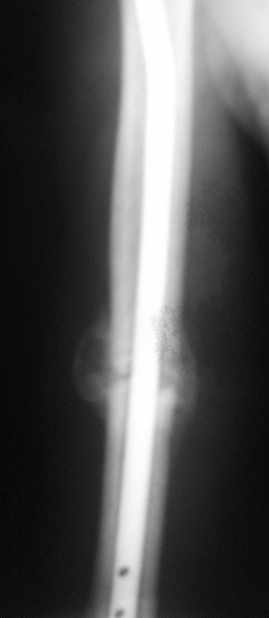

Уважаемые коллеги!Обратился пациент, оперирован не у нас.

однозначно не блокировать и не убирать - есть прекрасная мозоль и все отлично срастается. Мне плохо видно - выступает ли гвоздь проксимально ( кажется, нет, гвоздь строго в уровень с костью)?

Спасибо. А не слишком ли хороша мозоль?

Большая мозоль - здоровый организм УСПЕШНО компенсирует недостатки фиксации.

Само же состояние перелома мне не внушает никаких сомнений или опасений

Гвоздь для плеча - дело не очень хорошее, и, честно говоря, на этих снимках показаний к такому методу лечения я никаких не вижу. Больше процент несращений, часто (до 20-30 процентов) встречаются осложнения со стороны плечевого сустава... Однако, это уже выходит за пределы обсуждаемой темы

Пациент обратился с жалобой на лигатурный свищ.

Амплитуда движений 70-80% от контрлаптеральной конечности с умеренной болью в месте перелома. Наиболее болезненно - заведение руки за спину (появляется боль в области плечевого сустава). Отведение - градусов 70, далее за счет лопатки.

Обычное дело, пусть разрабатывает давно, лучше с методистом. Тут по снимкам проблем не видно. Винты вводить необязательно - если хирург знает, что делает. Например, если получился хороший press-fit из-за несоответствия формы гвоздя и канала.